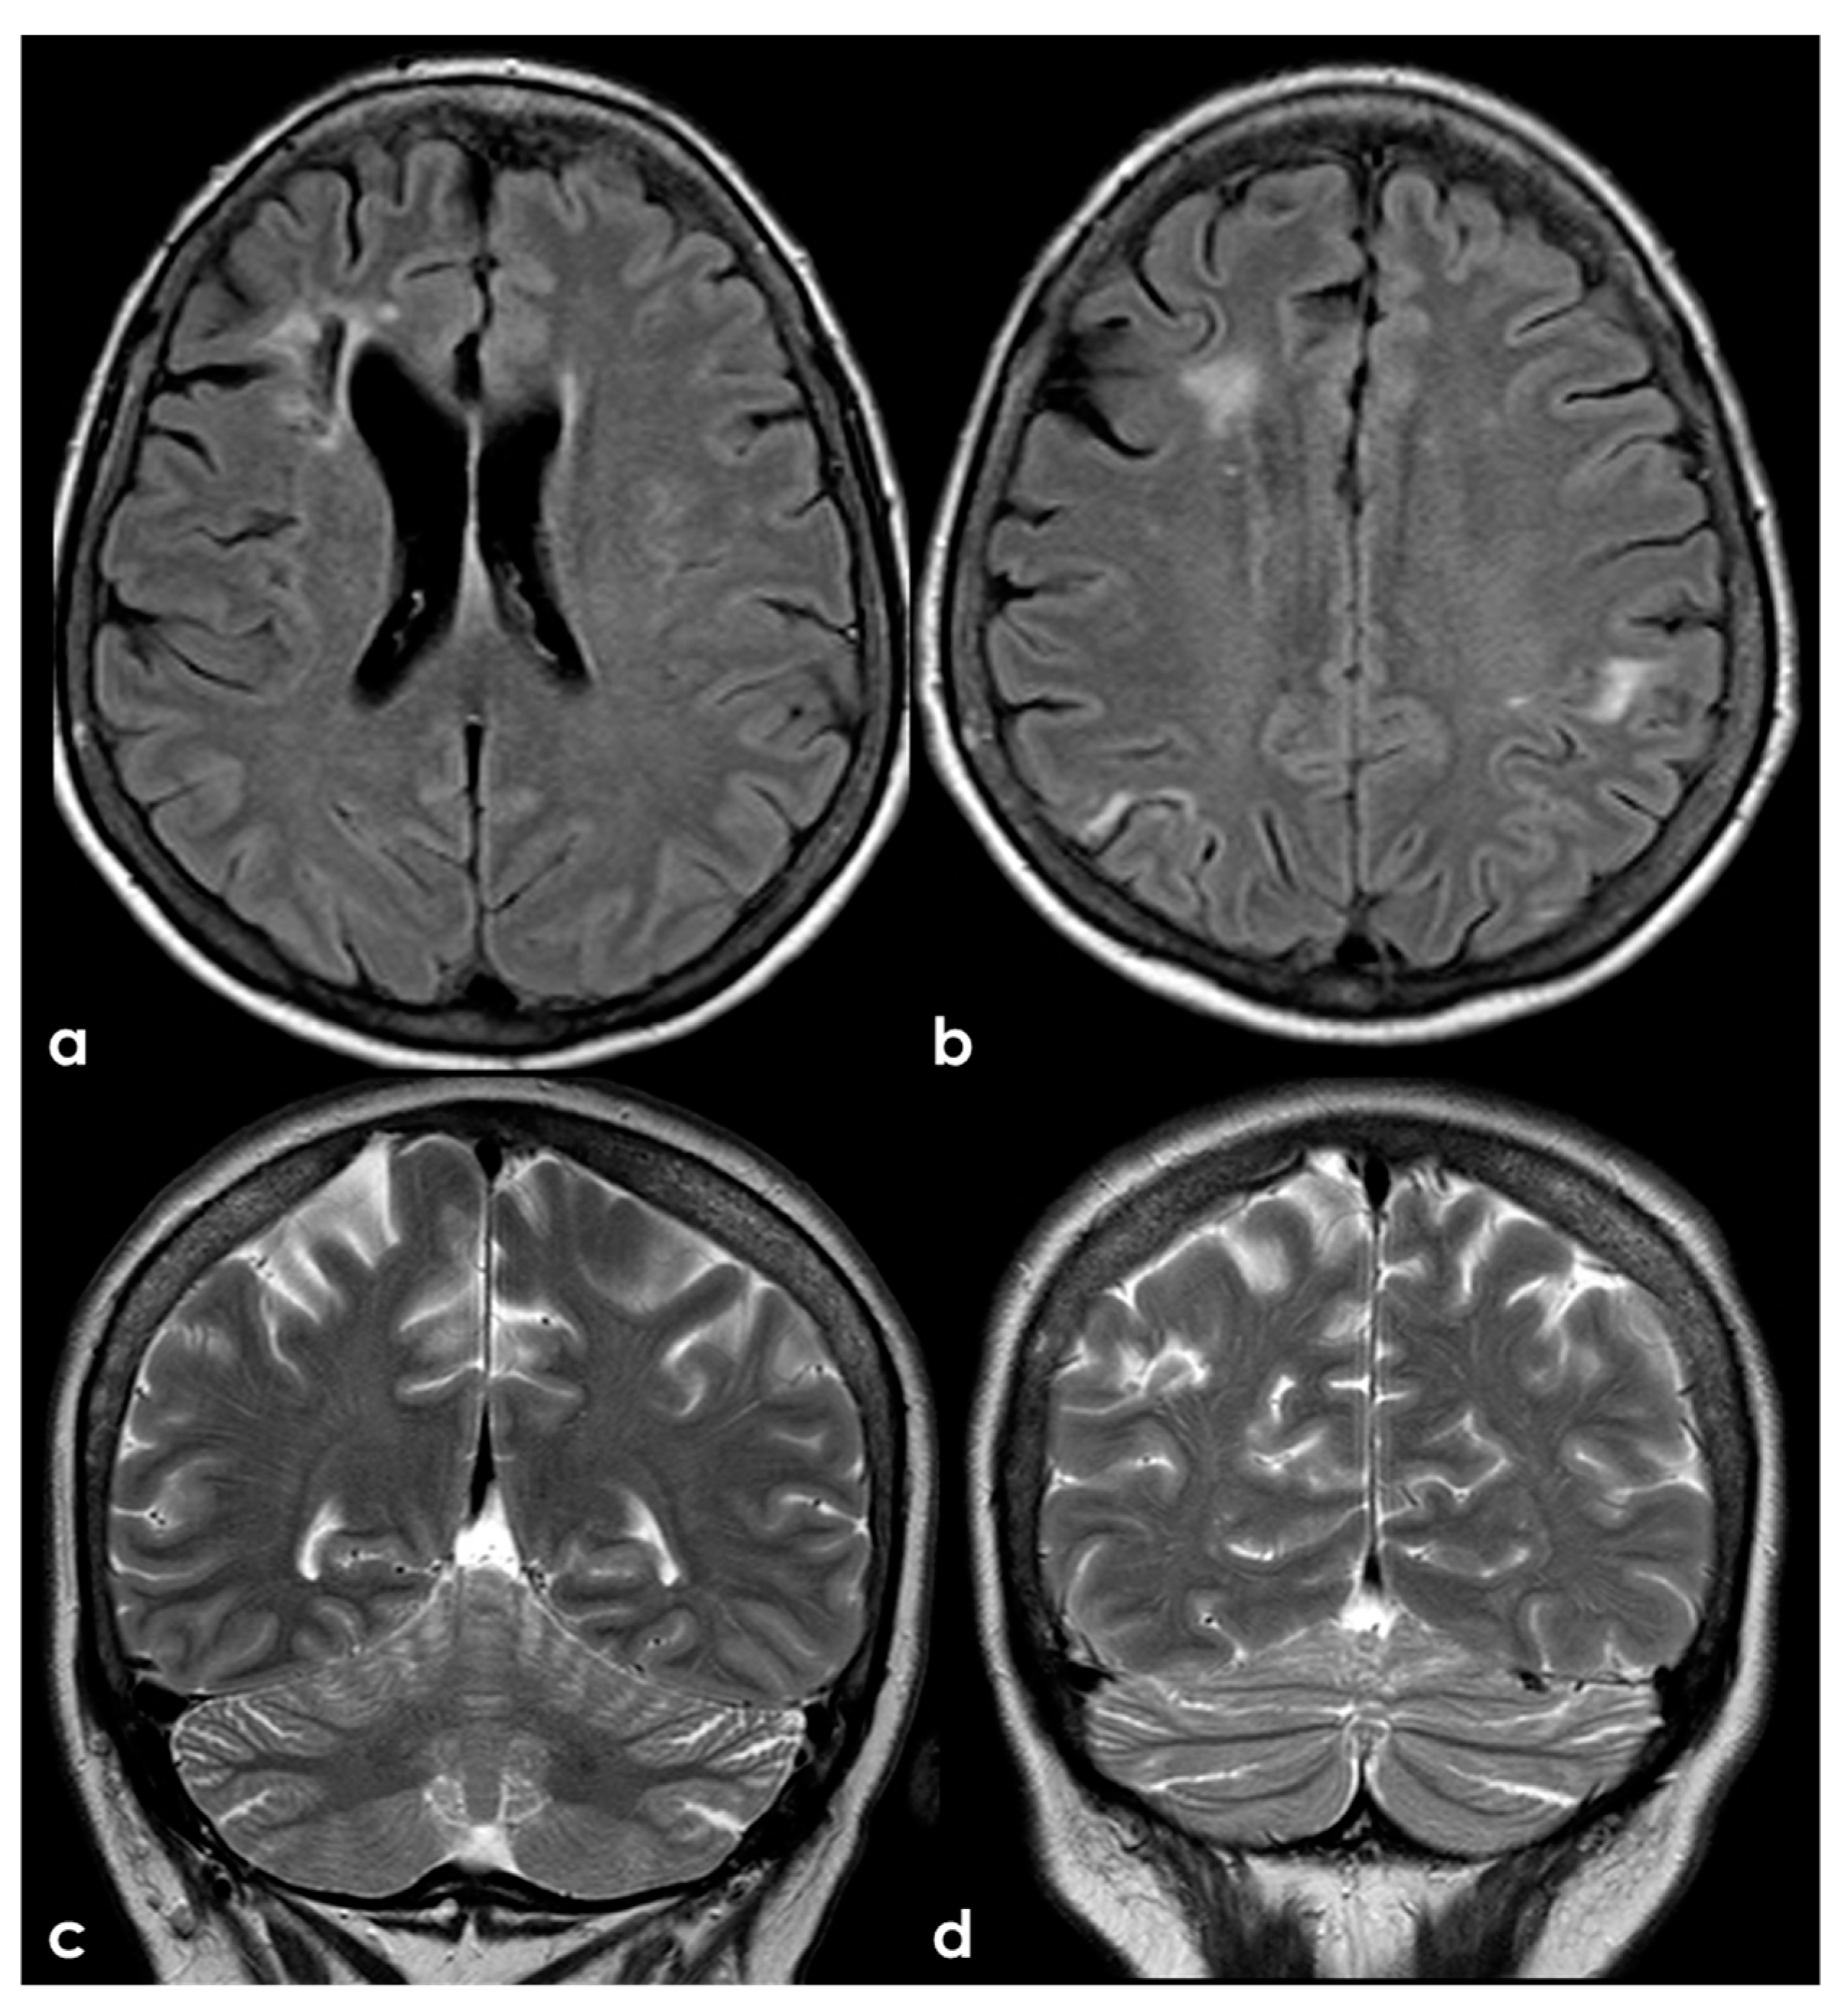

A different situation is illustrated in Figure 7, where the multiple ischemic lesions are in different vascular territories.

Figure 7.

Brain MRI (axial FLAIR in panels (a,b) and coronal T2W sequence in panels (c,d)) showing multiple cortico-subcortical ischemic lesions on both hemispheres and only few mildest SVD markers.